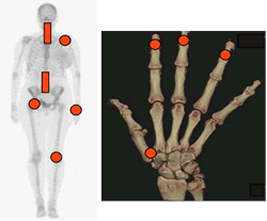

El compromiso articular es asimétrico y en las manos la afección tiene un predominio distal. En los casos avanzados, puede encontrarse deformidad. (Fig 5).

Fig 5. Distribución de la artropatía degenerativa.

Compromiso asimétrico de articulaciones grandes, columna cervical y lumbar.

En las manos predominio distal y de la articulación carpometacarpiana del 1 dedo.